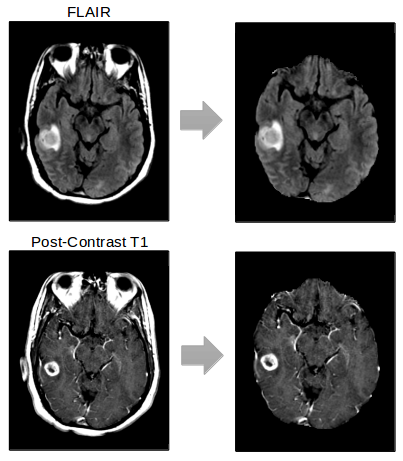

Standardized preprocessing methods are essential to deep learning pipelines that operate on medical images, as slight differences in preprocessing methods can lead to catastrophic prediction failures. DeepNeuro allows the user to preprocess data before inference using the Python object Preprocessor. Transformations applied in Preprocessor objects can be pure Python implementations, inference via neural networks, or links to outside programs such as 3DSlicer or ANTs [20]. These transformations can be applied to data held either in memory or loaded from a provided filepath, and can be returned as either Numpy arrays or stored back to disc. Preprocessors can be concatenated sequentially into preprocessing pipelines, or applied selectively to certain data objects and not others. Current Preprocessor objects available include 3D image registration (3DSlicer), 3D image resampling (3DSlicer), N4 Bias Correction (3DSlicer, ANTs), and skull stripping using a model trained with DeepNeuro (Figure 3).

Brain extraction or “skull-stripping” is a common image preprocessing step that is essential for many neuroimaging applications, including cortical parcellation and surface reconstruction. [34] Many effective, computationally-efficient tools exist for performing brain extraction. [35, 36, 37, 38, 39] However, their generalizability is limited in the presence of varying acquisition parameters or abnormal pathology, such as tumors. Without manual correction, poor brain extraction can introduce errors in downstream analysis. Using DeepNeuro’s U-Net architecture with the following parameters, we trained on a dataset of 30 glioma patients from a multi-institutional cohort, with manually-segmented brain masks (Figure 5). This patient cohort contained both pre-operative and post-operative patients.